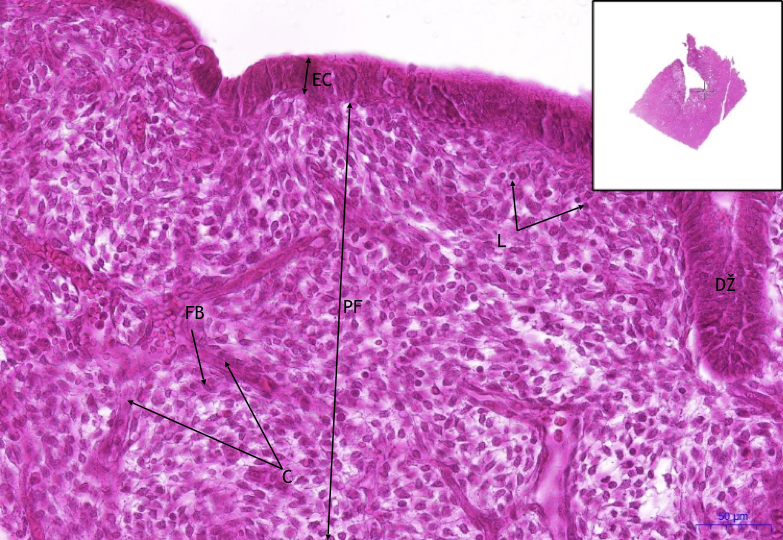

Рак шейки матки colli uteri in situ - фото презентация